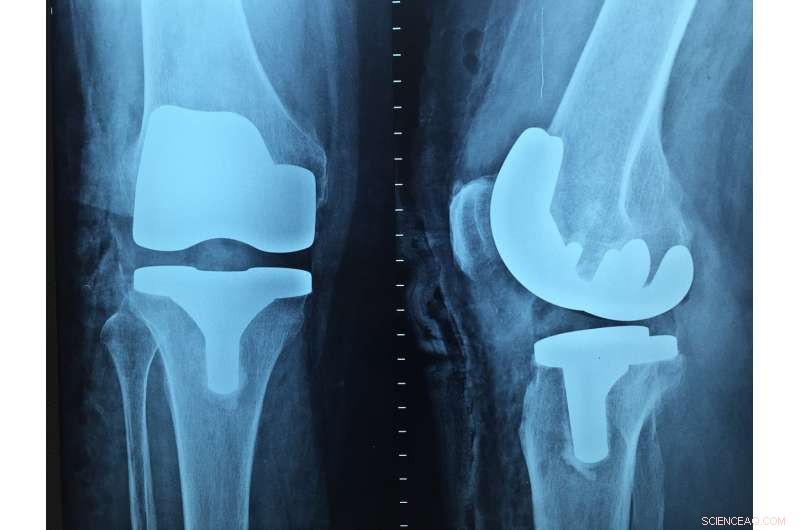

Metallic biomaterials are essential in prostheses that are subjected to high stresses, such as hip and knee prostheses. However, even the metals used in medicine provoke an immune reaction. The natural response of the body is to coat these metallic biomaterials with a kind of scar tissue that isolates the material from the surrounding functional tissues. This can facilitate infection in the area of the prosthesis.